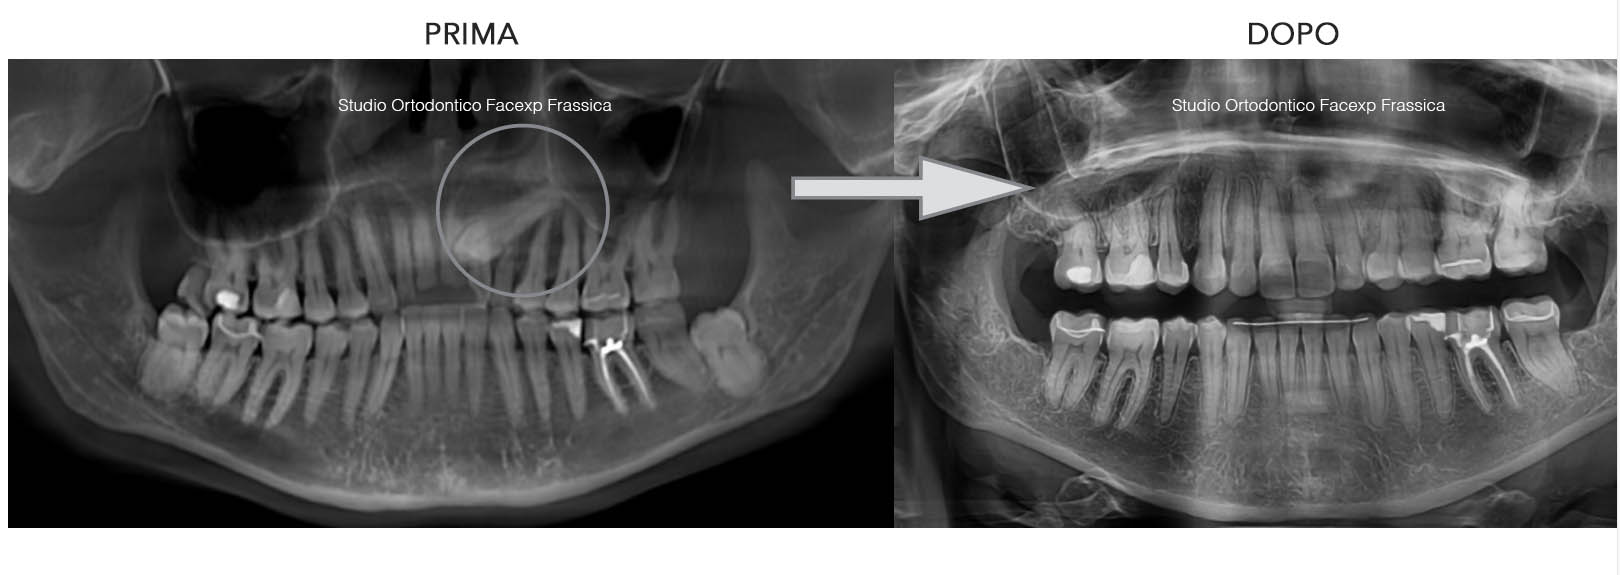

Michela: 40 anni

Un canino incluso non recuperabile e permanenza del canino da latte in arcata: trattata con estrazione del canino incluso e con la chiusura dello spazio estrattivo in maniera ortodontica, senza l’utilizzo di impianti dentali o altri denti “finti”. Finalizzazione dopo il trattamento ortodontico del settore frontale con sbiancamento e ricostruzioni estetiche in composito. 2 anni di trattamento.